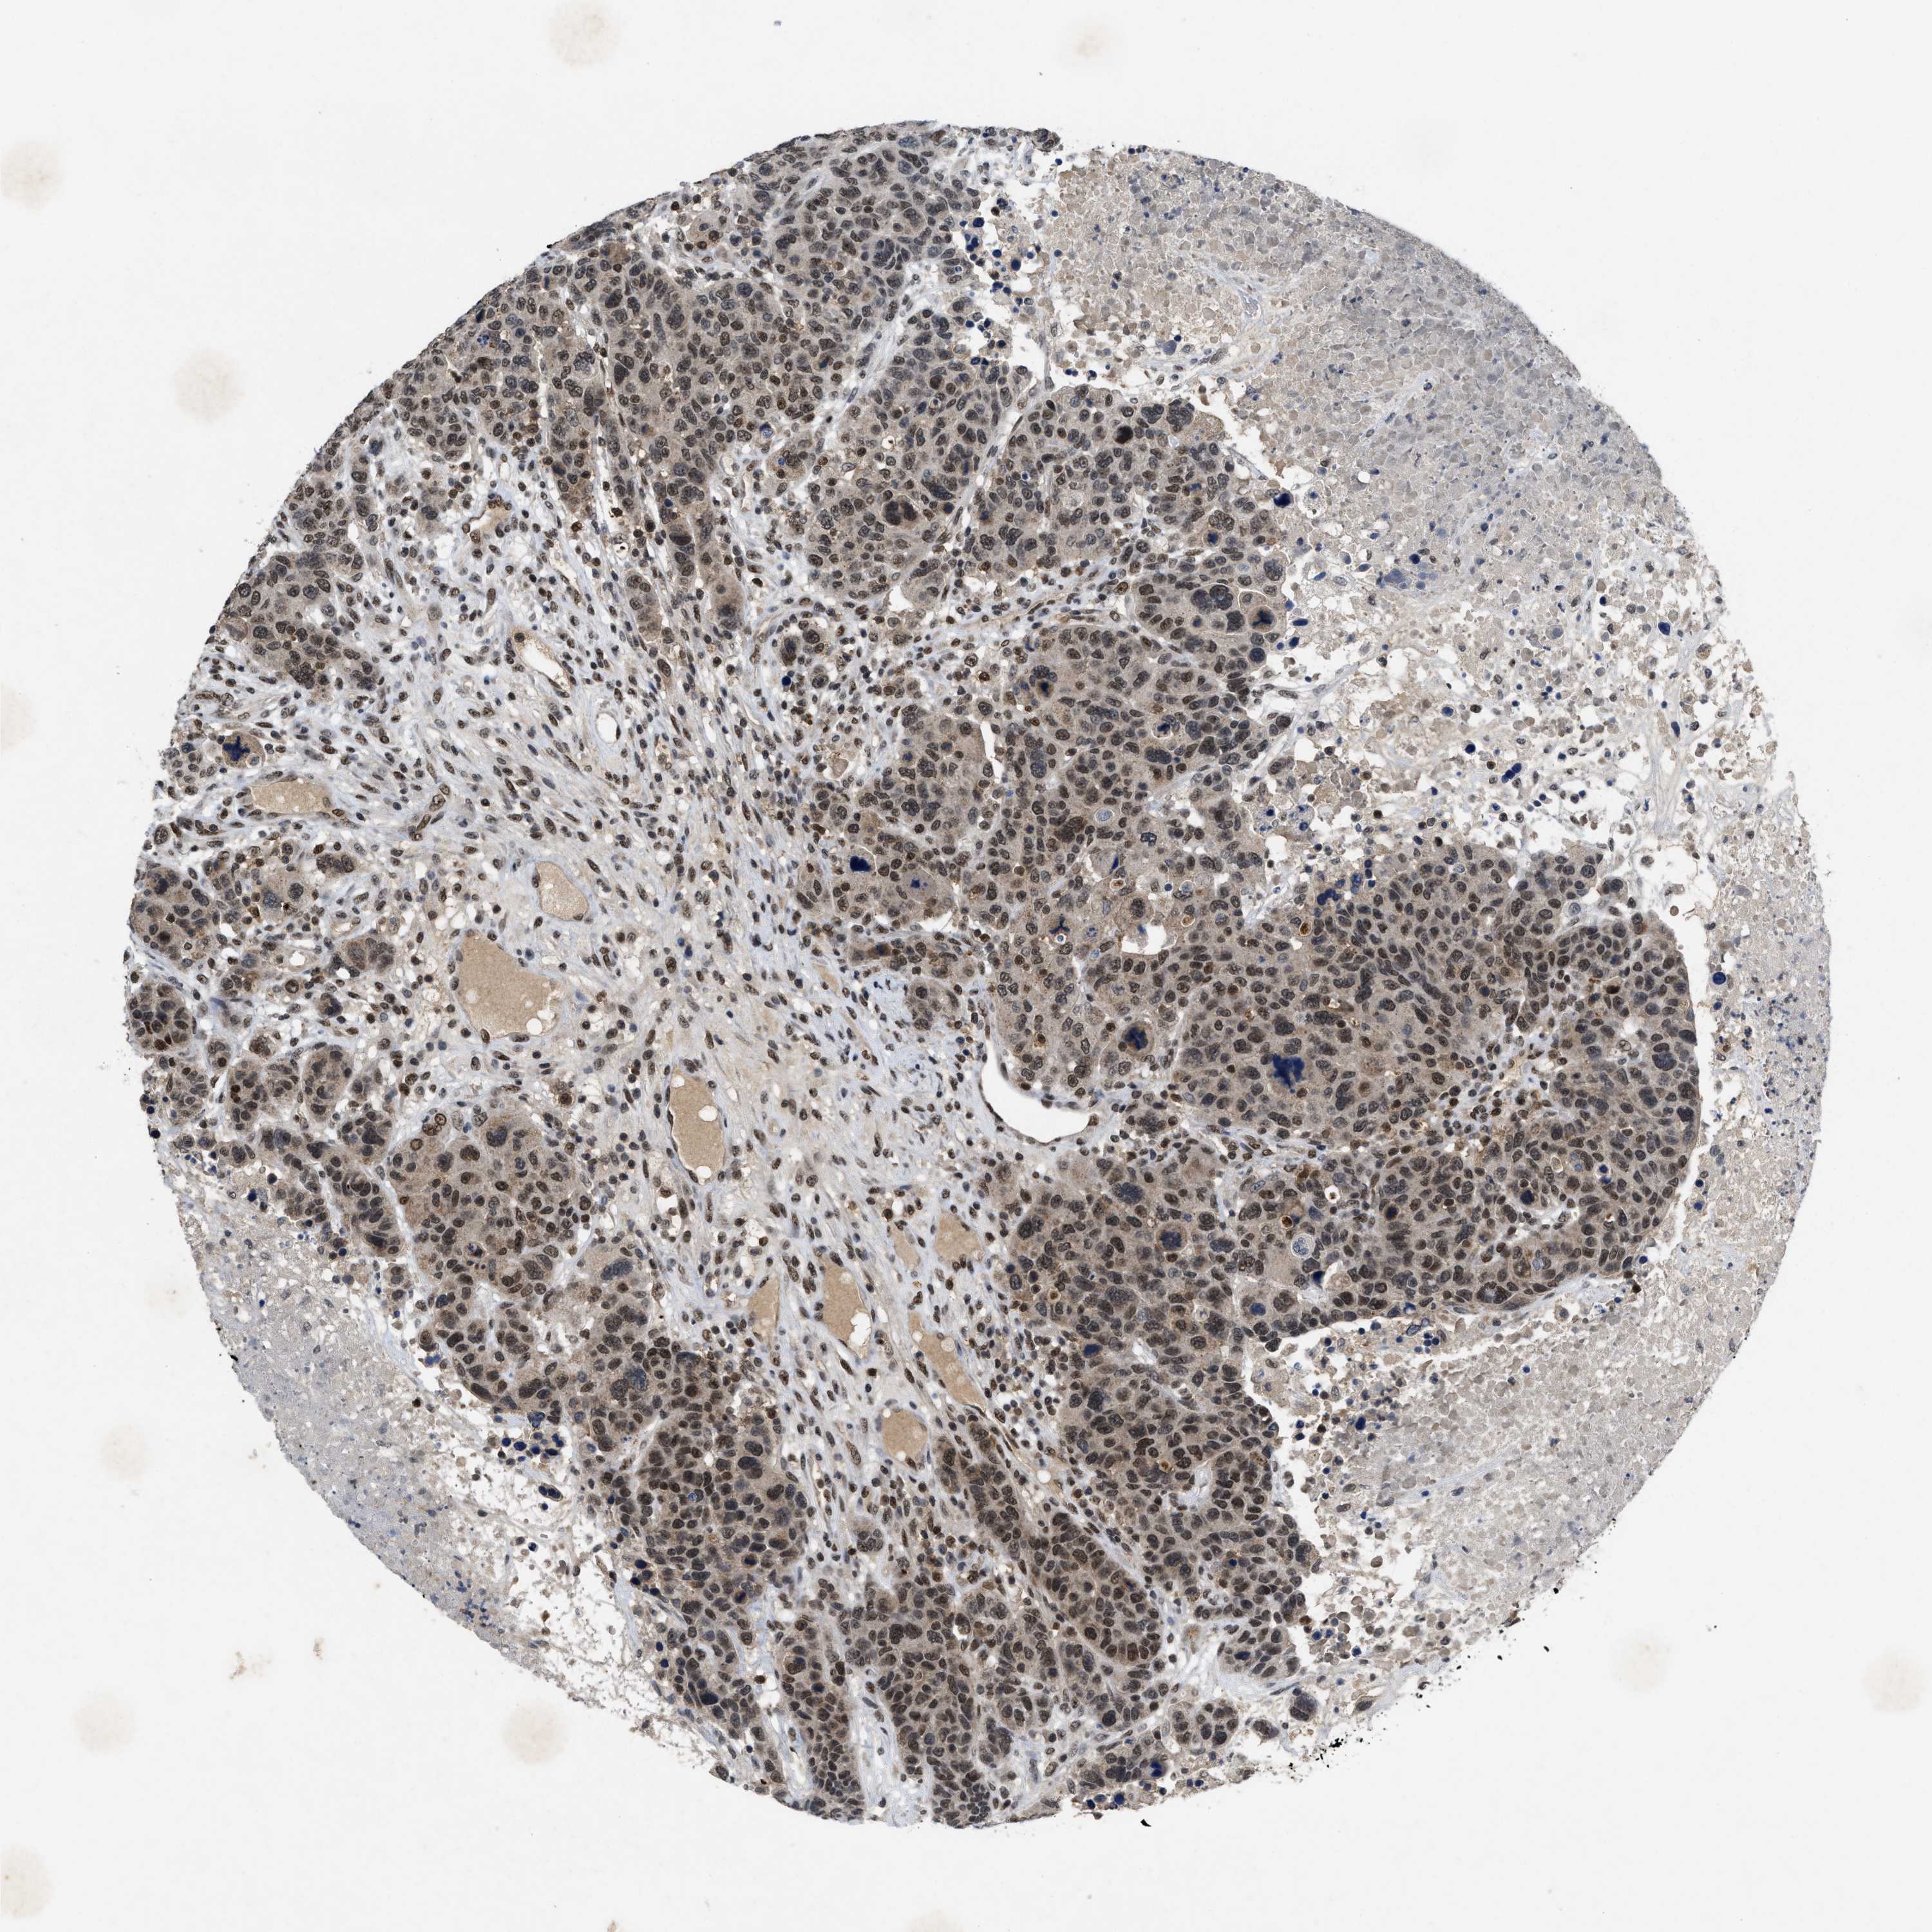

BRCA TCGA BRCA VALIDATION PROTEIN EXPRESSION